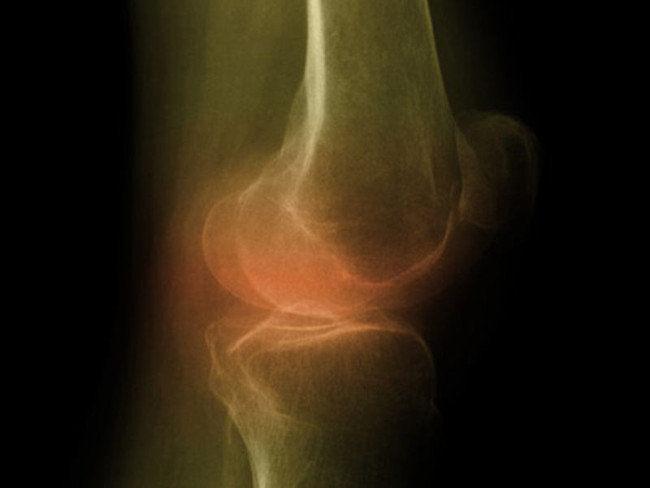

Lấy sụn từ mũi để phục hồi cho sụn đầu gối là một câu chuyện y học vừa được thí nghiệm thành công đang gây xôn xao giới y học trên toàn cầu.

Hai năm sau, 10 người này đã được chụp MRI khớp gối lần nữa cho thấy các mô sụn khớp gối làm từ sụn mũi đã phát triển thành mô mới, hoạt động bình thường, đầu gối của 9/10 người hoạt động linh hoạt hơn, bớt tình trạng đau hơn.